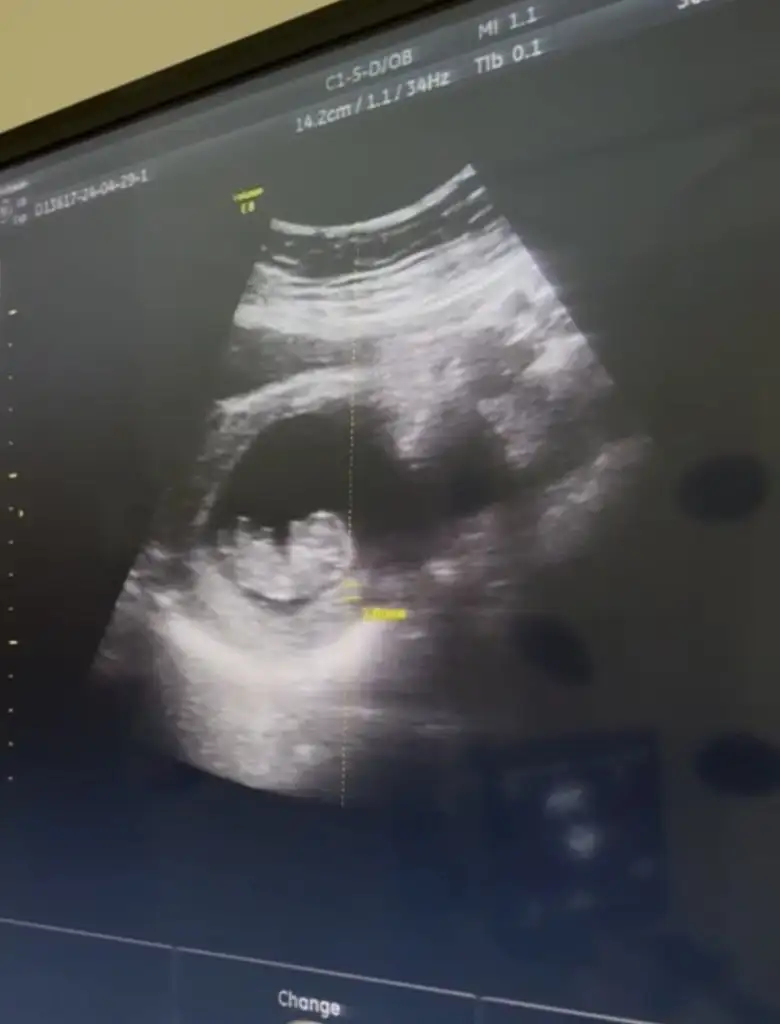

Kizlaaaat bizede tahminde bulunur musunuz doktor ilk kız dedi sonra çıkıntı görüyorum erkek dedi